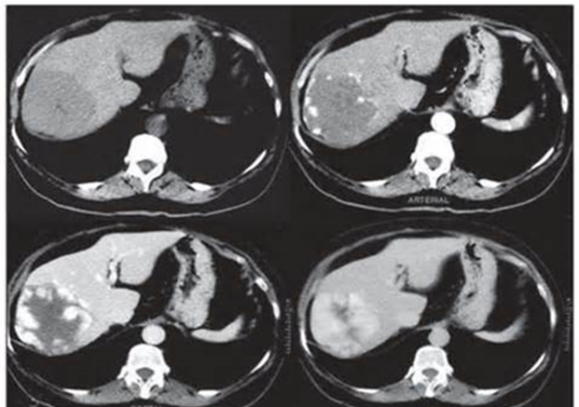

- Diaqnozu dəqiqləşdirmək üçün Qc venaları yoxlanılmalıdır. Bunun üçün dopler USM, KT-angioqrafiya, MRT-angioqrafiyalar və ya kontrastlı venoqrafiya edilir.

- Görüntüləmədə Qc venalarının trombotik tutulması diaqnozu dəqiqləşdirən əlamətdir.

PVT diaqnozunu dəqiqləşdirmək üçün portoqrafiya aparılır – Doppler USM, KT və ya MRT angioqrafiya.

- Kontrastlı müayinələrdə damarda tromb və ya kavernoz transformasiya

Qaraciyər venalarının görünməməsi, kontrastlaşmaması və ya trombla tıxanması.

- portoqrafiyada vena mənfəzində trombun görünməsi;

- venanın distalında genişlənmə və kavernoz transformasiyanın görünməsi;